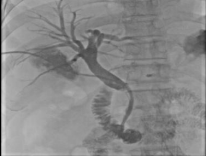

本次成功救治的两例患者,一例为胆总管中断恶性梗阻,另一例为胆总管下端结石嵌顿。面对肝内胆管不扩张的共同难题,我院介入团队果断采用了 “经皮经肝胆囊穿刺”这一技术路径。

1. 精准导航,一步到位:术前,通过磁共振胆管水成像(MRCP)精确绘制胆道“地图”,清晰显示梗阻部位与胆囊关系。术中,在超声实时引导下,采用经典的 Seldinger技术,犹如“穿针引线”,将穿刺针精准送入胆囊。值得一提的是,术中我们严格遵循安全路径,即经肝的右下周边穿刺,经胆囊床进入胆囊,此举有效避免了针道经过肝门等重要结构,相关并发症风险得以显著降低。 随后置入导丝、扩张通道、留置引流管,一步到位。